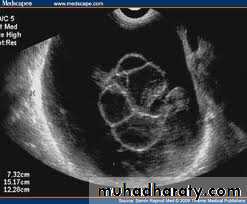

Ovarian dermoid cyst or Cystic teratomas:

Ultrasonography in Gynaecology

These ultrasound images reveal bilateral ovarian complex masses that contain both solid and cystic components. The right ovary shows a cystic mass with a solid, highly echogenic "dermoid plug". This is a solid nodule containing fat and various tissues including hair. Posterior acoustic shadowing is seen. The left ovary shows a dermoid plug and, in addition, a "dermoid mesh" is also seen, an irregular echogenic solid mass within the cyst. Echogenic debris is seen floating within the fluid

• Ovarian dermoid cyst or Cystic teratomas: